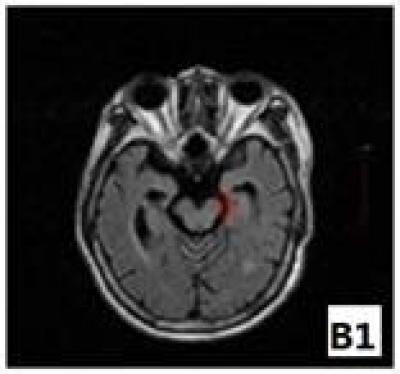

Negative motor evoked potentials after cerebral infarction, indicative of poor recovery of limb motor function, tend to be accompanied by changes in fractional anisotropy values and the cerebral peduncle area on the affected side, but the characteristics of these changes have not been reported. As reported previously, the lower limit value of fractional anisotropy of the cerebral peduncle in healthy volunteers is 0.36, and the lower limit of the asymmetry of the cerebral peduncle area is 0.83. It is worth further investigating the effects of the lower limit value of the cerebral peduncle on limb motor functional recovery in stroke patients. Dr. Zhibin Song and coworkers from Xiaolan Hospital of Southern Medical University, China mainly investigated the relationship between characteristics of cerebral peduncle fractional anisotropy values and area on the affected side and limb motor function recovery in patients with negative motor evoked potential after cerebral infarction. Their results showed that the fractional anisotropy values in the cerebral peduncle in patients with negative motor evoked potentials after cerebral infarction decreased most obviously within 1 months after disease onset, and the drop critical value of fractional anisotropy value of 0.36 occurred during this time period, indicating poor limb motor function recovery; patients with negative motor evoked potentials after cerebral infarction presented with a shrunken area of the cerebral peduncle on the affected side at 6 months after disease onset, and even worse outcomes in the subsequent months until 12 months, with a lower limit value of area asymmetry of 0.83, indicating poor limb motor function recovery. These findings, published in the Neural Regeneration Research (Vol. 8, No. 29, 2013), revealed the stroke patients with negative motor evoked potential show poor limb motor function recovery.

Article: " Why do stroke patients with negative motor evoked potential show poor limb motor function recovery?" by Zhibin Song1, Lijuan Dang1, Yanling Zhou1, Yanjiang Dong1, Haimao Liang1, Zhengfeng Zhu1, Suyue Pan2 (1 Department of Neurology, Xiaolan Hospital of Southern Medical University, Zhongshan 528415, Guangdong Province, China; 2 Department of Neurology, Nanfang Hospital of Southern Medical University, Guangzhou 510515, Guangdong Province, China)

Song ZB, Dang LJ, Zhou YL, Dong YJ, Liang HM, Zhu ZF, Pan SY. Why do stroke patients with negative motor evoked potential show poor limb motor function recovery? Neural Regen Res. 2013;8(29):2713-2724.